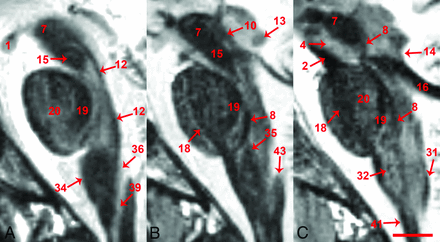

The FGATIR sequence provided novel MR imaging–derived contrast throughout the in vivo brain stem and allowed the direct identification of many small functionally important structures. Structure identification by 2 neuroradiologists was facilitated by 3-plane cross-referencing. Selected serial axial images illustrate contrast resolution of internal brain stem anatomy at canonical levels (Fig 1). Selected coronal and sagittal images also reveal excellent contrast resolution of internal brain stem anatomy (Figs 2 and 3, respectively). Such longitudinal images demonstrate the superior-inferior course of several brain stem pathways and the potential for the 0.8-mm isotropic FGATIR to enhance our understanding of the 3D organization of the brain stem. Videos of axial, coronal, and sagittal images through the brain stem are provided to interested readers on-line (On-line Videos 1–3).

Medial-to-lateral sagittal in vivo MR images parallel to the interhemispheric plane and ventral medullary fissure for the brain stem including 1.2-, 2-, and 6-mm lateral to the midline (A, B, and C, respectively). A 26-year-old healthy control female subject, 0.8-mm isotropic resolution, 9 individual datasets coregistered and averaged, 2× imaging sessions, ∼2-hour 15-minute total scan time (scale bar = 5 mm). Please see the Table and results section for explanation of labeled structures.

Labeling in the figures emphasizes unambiguous structures that can be identified well on the images. Most of these labeled structures are well-known to clinicians familiar with brain stem anatomy (eg, the medial longitudinal fasciculus). Directly labeled visible structures also can be used to generate more exact indirect localization for other bordering internal brain stem structures. Figure 4 provides a highly detailed example of this approach for the inferior midbrain where the likely positions of multiple additional structures can be estimated relative to the borders and anatomic spaces formed between the medial longitudinal fasciculus, medial lemniscus, and decussation of the superior cerebellar peduncles. Annotation at this level of detail with descriptions of functional relevance is possible throughout the brain stem, but is beyond the scope of this initial report. Other selected examples of indirect localization that may be of general interest include the oculomotor complex (bright region posteromedial to the central tegmental tract in Fig 1A), pedunculopontine nucleus (bright region medial to the medial lemniscus and lateral to the decussation of the superior cerebellar peduncles, in Fig 1B), locus coeruleus (bright region posterior to the central tegmental tract and medial to the superior cerebellar peduncle in Fig 1C), and facial nucleus (bright region posterolateral to the central tegmental tract and medial to the cerebellar peduncles in Fig 1F). An inferior notch along the medial aspect of the left middle cerebellar peduncle with gray matter signal intensity in Fig 2D is the cochlear nucleus.

There also are subtle features in the images that are difficult to assign with certainty (and sometimes only visualized on 1 side) that likely correspond to specific structures better resolved with postmortem MR microscopy53 and histology atlases.48⇓–50 Limited visualization may be from partial volume effects due to the small size of the structures relative to 0.8-mm isotropic voxels and/or less contrast relative to surrounding nervous tissue. On the right side of Fig 1B, there is an arc-like medially concave dark structure oriented anterior-posterior, consistent with the expected location of the left oculomotor nerve. In Fig 1C, -D, the tectospinal tract appears as a faint dark dotlike structure anterior to the medial lemniscus, particularly on the left side. In Fig 1E, the left tectospinal tract is more obvious, but there is marked asymmetry compared with the subject’s right side. Also, in Fig 1E, the indistinct anterior margin of the medial lemniscus may represent the anteromedial continuation of the trapezoid body. In Fig 2D, an intermediate signal intensity line oriented inferomedial to superolateral, dividing the area postrema (on the right side of the image), may be the sulcus limitans. Some structures also are better recognized when the imaging plane is transverse to the structure. For example, the facial nerve in the lateral midpons is difficult to appreciate in the axial plane (Fig 1F), but better resolved in the coronal plane (Fig 2D).